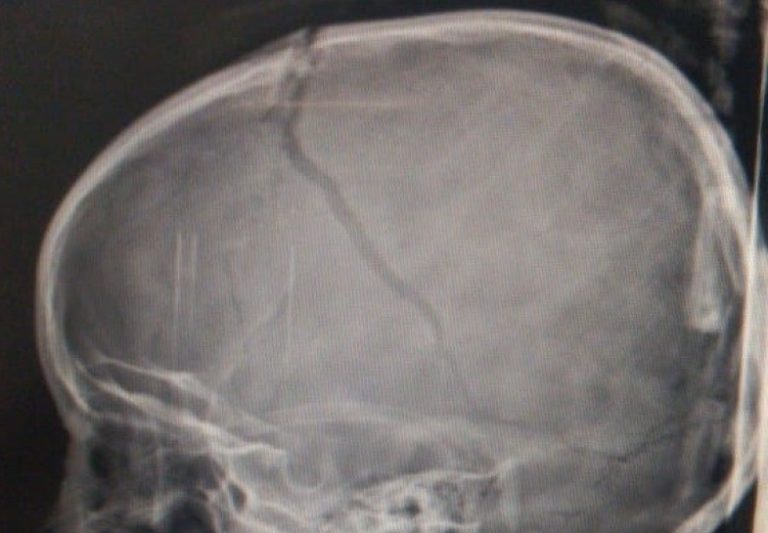

L.T.A, a menina de 5 anos que caiu do toboágua no Clube Recreio Colonial, em Catalão, na tarde deste sábado (11), continua internada na Unidade de Terapia Intensiva (UTI) do Hospital de Urgências de Goiânia Governador Otávio Lage de Siqueira (HUGOL). A garota, que sofreu um grave traumatismo craniano, está em coma induzido. Apesar de ter sofrido uma hemorragia, seu estado de saúde é considerado estável. A família tem esperança que o inchaço no cérebro de L. ceda nas próximas horas.